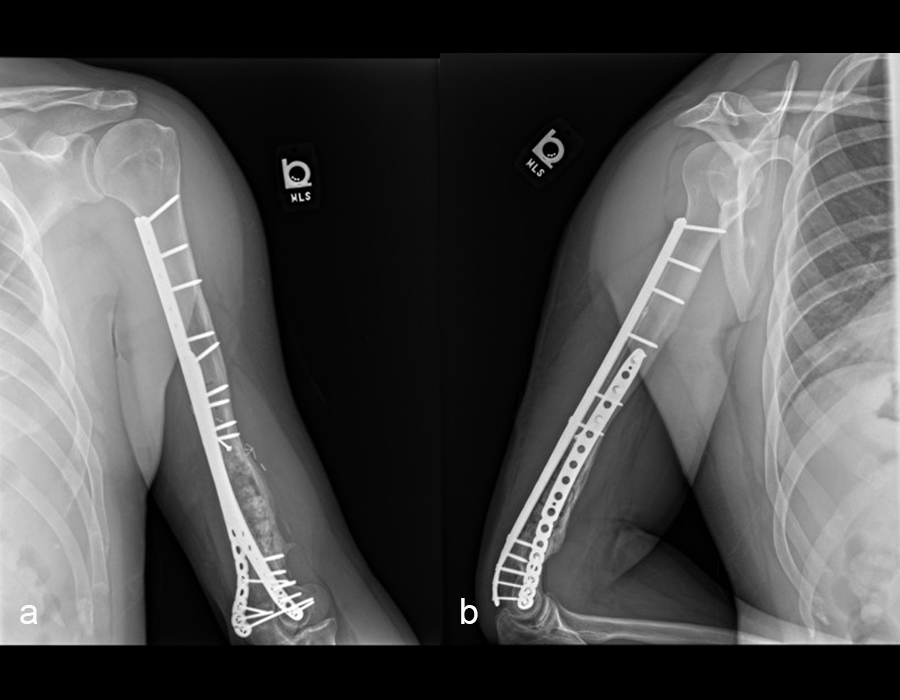

The second stage of surgery took place in October 2022. The cage was inserted (Figs 20-22) and filled with ~20cc autograft obtained by RIA of the femur, 30cc allograft and 3cc BMAC.

Healing progressed well over the following 9 months (Fig 23 - 27). The patient’s pain was well controlled in the early postoperative phase, and he was weaned off the prescribed narcotics after four weeks. He remained smoke free for the first four weeks and then admitted to re-starting his vaping. His elbow ROM improved significantly to 20-125 and good supination/pronation.